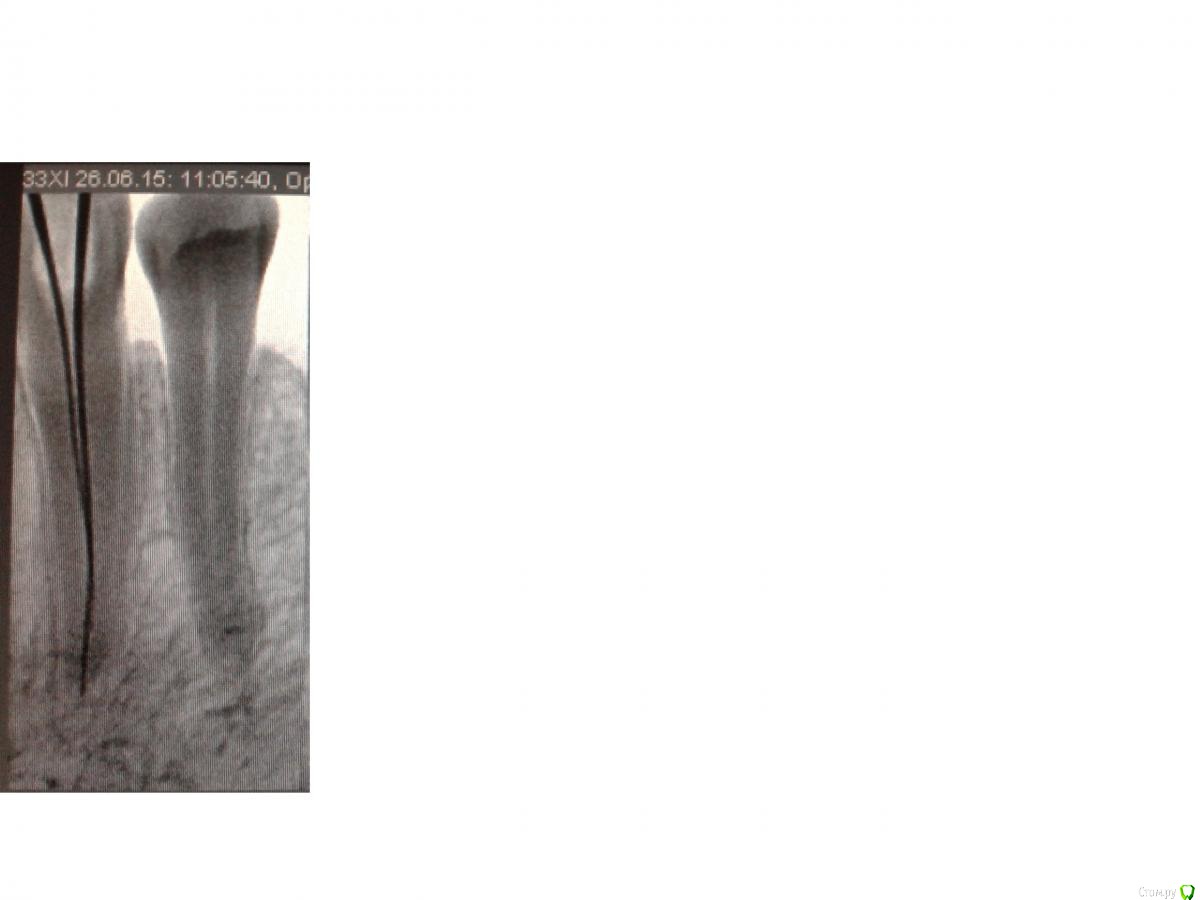

mariskus71 Опубликовано 25 августа, 2015 Автор Поделиться Опубликовано 25 августа, 2015 (изменено) Если Вы об этом - то это не канал , а контуры костной перегородки между этим и соседним зубом. А снимки выкладывайте, посмотрим.Спасибо Вам большое,сняли груз с души,а то я уж думала,что дополнительный канал не запломбировали.Выкладываю снимки.Первый снимок был сделан после пломбировки временным каласептом.Второй перед пломбировкой прошли канал и нашли дополнительный.А на последнем врач отметил непонятные участки (со вторым я поняла,а вот с первой цифоркой то же непонятно)Спасибо Изменено 25 августа, 2015 пользователем mariskus71 Ссылка на комментарий

St. Опубликовано 25 августа, 2015 Поделиться Опубликовано 25 августа, 2015 Пожалуйста) По снимку с инструментами всё хорошо. По тому который после пломбировки - тоже.Что врач хотел отметить - не знаю.Как сейчас ведет себя зуб? Неприятные ощущения уменьшаются? Ссылка на комментарий